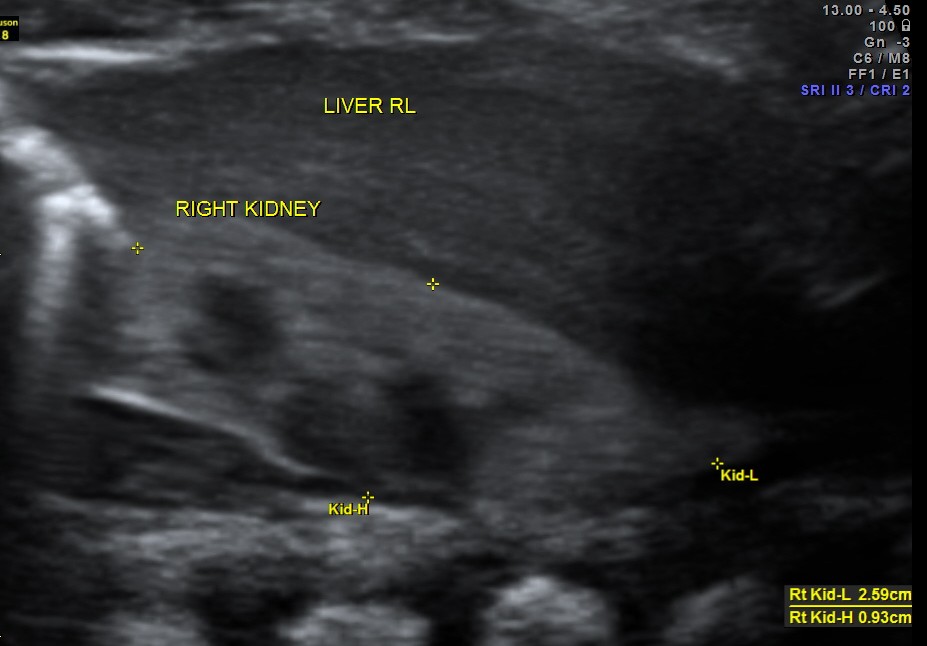

https://kriznanultrasoundimages.com/2013/05/12/tetralogy-of-fallot-tof/ at this time there was a revision of the cardiac findings : LEFT ATRIAL ISOMERISM WITH TETRALOGY OF FALLOT The irregular rhythm was not made out now. Apart from this the foetus has symmetrical IUGR and oligohydramnios Now the child was brought when she was 51 days old . She was born prematurely at 33 weeks of gestation . She had been seen at three higher institutions . The paediatric cardiologist has given a working diagnosis of CONO TRUNCAL VSD. But the catch was that the child had renal dysfunction with s .creatinine around 2 mgms and the ultrasound could not visualise the left kidney. The right kidney was reported to be hyperechoic . The following 2 pictures were of the fetal kidneys , as seen during the scan earlier.

The following two pictures show the hyperechoic kidneys of the child with mild pelvi calyceal dilatation . The kidneys were picked up only with the 11 mhz transducer.